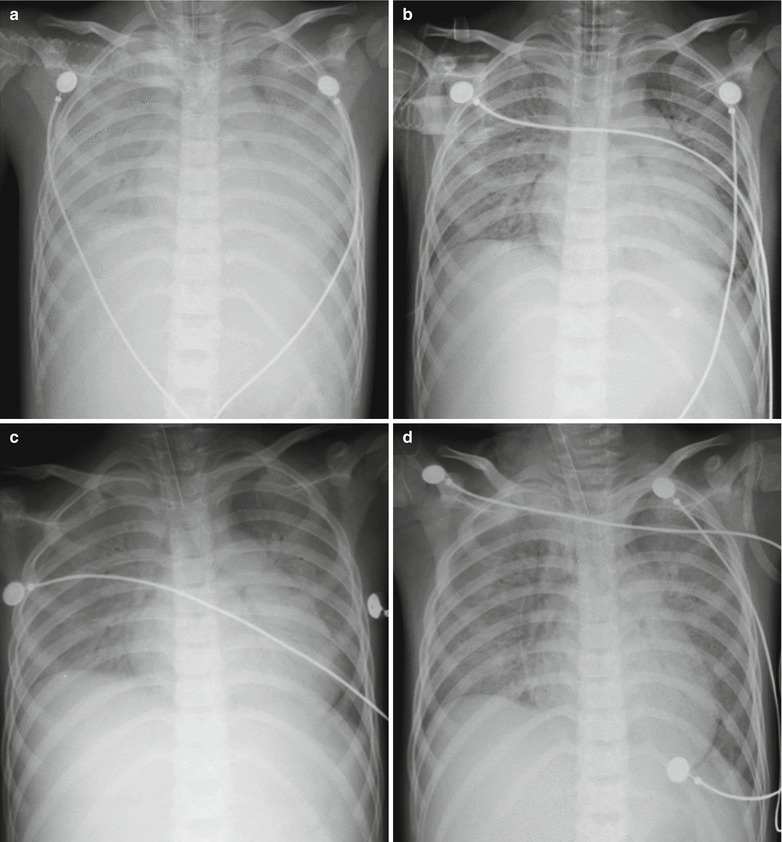

Measles Complicated by Pneumonia in Adults

X-Ray

X-ray demonstrates flakes and patches of blurry shadow in both lower lungs, indicating lobular pneumonia. With the progress of the inflammation, the lesions may fuse into large flakes of consolidation shadows. Some lesions might progress rapidly into multi-lobular inflammatory infiltration, with demonstrations of extensive, polymorphic, different sized, and unevenly distributed large flakes of consolidation shadows in the lungs. There are also pleural thickening and a small quantity of pleural effusion. In rare cases, formation of pulmonary bulla, mediastinal emphysema, and subcutaneous emphysema might be demonstrated.

CT Scanning

CT scanning demonstrates pulmonary consolidation, thickened bronchial vascular bundles, ground-glass opacity, lesions at the lobular center, and nodular shadows (Figs. 23.18 and 23.19). In rare cases, cords like shadow can be demonstrated, with accompanying pleural effusion.

Fig. 23.18.

Pediatric measles complicated by pneumonia. (a) X-ray demonstrates multiple flakes of shadows in both lungs, blurry hilar shadow at both lungs, and blurry left costophrenic angle. (b) By reexamination after treatment for 1 day, X-ray demonstrates slightly extended range with shadows at both lungs. (c–h) By reexamination after treatment for 3 days, CT scanning demonstrates multiple large flakes of consolidation lesions in both lungs with inner air bronchus sign. (i) By reexamination after treatment for 8 days, the lesions are demonstrated to be absorbed and improved. X-ray demonstrates shrinkage of the range with lesions, decreased density of the lesions, quite clearly defined hilum at both lungs, and well-defined bilateral costophrenic angles

Fig. 23.19.

Adult measles complicated by pneumonia. At day 2 after hospitalization, CT scanning demonstrates ground-glass opacity in the apical posterior segment of the left upper lung lobe

Adult measles complicated by pneumonia. (a–d) Plain CT scanning demonstrates multiple nodular shadows with different size in both lungs (Note: The case and the figures were provided by Wu JP and Yun J from the Third People’s Hospital, Changzhou, Jiangsu, China)

The annual incidence rate of measles has decreased by over 99 % due to the vaccination of attenuated live vaccine. However, sporadic cases or community-based outbreaks in adults tend to increase in recent years due to missed vaccination or invalid vaccination, mostly with measles viral pneumonia or bacterial pneumonia secondary to measles. Pulmonary infections in the cases of measles are mainly primary measles viral pneumonia, and measles can cause pulmonary lesions via two routes: the first route is via direct infection of measles virus and the other is secondary bacterial or other pathogenic infections. Only 3–4 % of the cases of measles pneumonia are primary, which is known as simplex measles viral pneumonia. Most other cases are secondary. According to literature reports, Haemophilus and Neisseria meningitidis are the most common pathogens. Jia CY et al. reported 163 cases of measles in adults. They found that only 3–4 % of the cases sustain pneumonia, in agreement to the previous findings, accounting for 1.7 % of the cases infected by measles virus during the same period. And the severe cases account for 6.1 % of infected adults in the same period. In addition, secondary bacterial infection and complications might occur in most patients.

Based on recent studies, it is believed that immune mechanism is the main pathophysiological factor contributing to the occurrence of measles pneumonia. In children, measles pneumonia often occurs when immune defense fails to fight against the invasion. However, in adults, measles pneumonia often occurs in pregnant women and patients with compromised immunity, such as patients receiving the treatment for hepatopathies and organ transplantation, patients with HIV/AIDS, and patients receiving immunosuppressive treatment. Qaisar reported that the incidence rate of complications of measles is closely related to the nutrition of the pediatric patients, indicating certain relationship between measles pneumonia and the immunity. Histological studies indicated that in the cases with no complications, the patients with simplex measles virus pneumonia are demonstrated with proliferation of alveolar epithelium and extensive alveolar lesions. The epithelial proliferation is related to the alveolar squamous metaplasia around the bronchioles and bronchi. Cystic dilatation of bronchial mucous gland can be observed, which is characterized by multinucleated giant cells at the alveolar, bronchiolar, and bronchial epithelium. The imaging demonstrations of measles pneumonia resemble to those of other viral pneumonia. Simplex measles virus pneumonia might be demonstrated as reticular nodular shadow, consolidation of the air cavity, and sometimes enlarged hilar lymph nodes in children. CT scanning demonstrates ground-glass opacity, consolidation of the air cavity, and nodules at the center of lobule. The concurrent interstitial and parenchymal lesions indicate the pathological basis of extensive damages to the alveoli. In rare cases, pleural effusion can be observed. Complications may be demonstrated as corresponding lesions, such as pneumothorax, subcutaneous emphysema, and pulmonary edema.